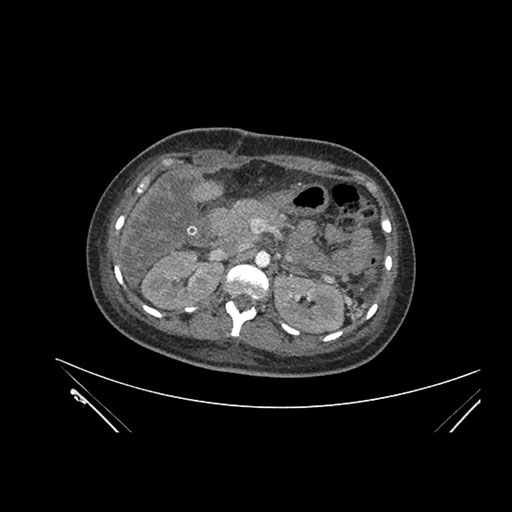

Imaging Analysis

Look through the patient's CT scan to identify any areas of concern for the necessary procedure.

Axial Arterial

Based on initial findings, which issue(s) would you be most concerned about?